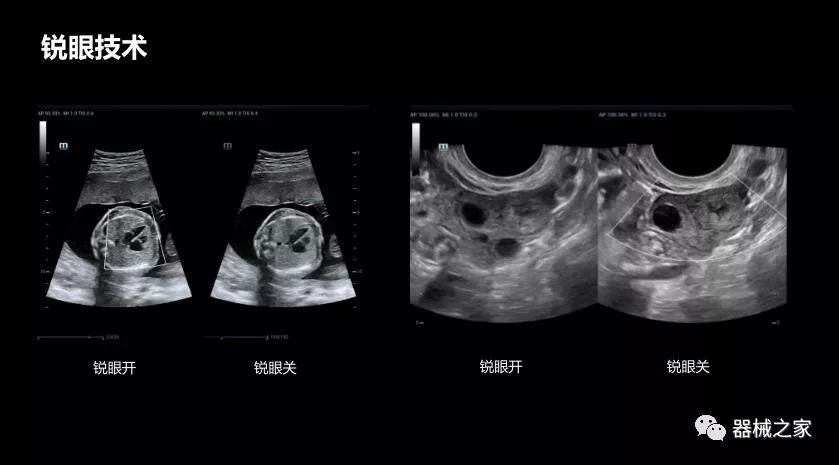

銳眼技術

做胎兒心臟檢查的時候,如果是聲窗不好的孕婦,很難看清胎兒心腔 。女媧Resona 8的銳眼技術能很好的優(yōu)化心腔內的噪聲,讓胎心結構完美的呈現。